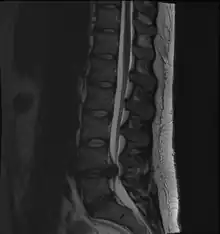

Narrowed space between L5 and S1 vertebrae, indicating probable prolapsed intervertebral disc - a classic picture.

• Magnetic resonance imaging is the gold standard study for confirming a suspected LDH. With a diagnostic accuracy of 97%, it is the most sensitive study to visualize a herniated disc due to its significant ability in soft tissue visualization. MRI also has higher inter-observer reliability than other imaging modalities. It suggests disc herniation when it shows an increased T2-weighted signal at the posterior 10% of the disc. Degenerative disc diseases have shown a correlation with Modic type 1 changes. When evaluating for postoperative lumbar radiculopathies, the recommendation is that the MRI is performed with contrast unless otherwise contraindicated. MRI is more effective than CT in distinguishing inflammatory, malignant, or inflammatory etiologies of LDH. It is indicated relatively early in the course of evaluation (<8 weeks) when the patient presents with relative indications like significant pain, neurological motor deficits, and cauda equina syndrome. Diffusion tensor imaging is a type of MRI sequence used for detecting microstructural changes in the nerve root. It may be beneficial in understanding the changes that occur after herniated lumbar disc compresses a nerve root, and might help in differentiating the patients that need surgical intervention. In patients with a high suspicion of radiculopathy due to lumbar disc herniation, yet the MRI is equivocal or negative, nerve conduction studies are indicated.[43] T2-weighted images allow for clear visualization of protruded disc material in the spinal canal.

The majority of spinal disc herniations occur in the lumbar spine (95% at L4–L5 or L5–S1).[20] The second most common site is the cervical region (C5–C6, C6–C7). The thoracic region accounts for only 1–2% of cases. Herniations usually occur postero-laterally, at the points where the annulus fibrosus is relatively thin and is not reinforced by the posterior or anterior longitudinal ligament.[20] In the cervical spine, a symptomatic postero-lateral herniation between two vertebrae will impinge on the nerve which exits the spinal canal between those two vertebrae on that side.[20] So, for example, a right postero-lateral herniation of the disc between vertebrae C5 and C6 will impinge on the right C6 spinal nerve. The rest of the spinal cord, however, is oriented differently, so a symptomatic postero-lateral herniation between two vertebrae will impinge on the nerve exiting at the next intervertebral level down.[20]

Lumbar disc herniations occur in the back, most often between the fourth and fifth lumbar vertebral bodies or between the fifth and the sacrum. Here, symptoms can be felt in the lower back, buttocks, thigh, anal/genital region (via the perineal nerve), and may radiate into the foot and/or toe. The sciatic nerve is the most commonly affected nerve, causing symptoms of sciatica. The femoral nerve can also be affected and cause the patient to experience a numb, tingling feeling throughout one or both legs and even feet or a burning feeling in the hips and legs.[21] A herniation in the lumbar region often compresses the nerve root exiting at the level below the disc. Thus, a herniation of the L4–5 disc compresses the L5 nerve root, only if the herniation is posterolateral.